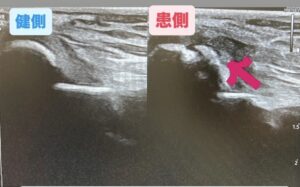

左側が健側の左肘。右側が患側の右肘です。

骨が剥がれかけているのが確認できますが、治って来ているのが確認できます。